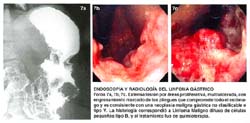

Se consignan fotos representativas del Linfoma Gástrico en composiciones de la Foto 1 a la Foto 7.

Si tenemos en cuenta que la mayoría de los pacientes que acuden al INEN con Linfoma gástrico tienen una forma endoscópica de cáncer avanzado (76.9%), esto es, principalmente de formas ulceradas-infiltrantes o tumores inclasificables, no es de extrañar entonces que se suelan acompañar de anemia, hipoalbuminemia, hipoproteinemia y que haya una manifestación de elevación de DHL en un grupo significativo de los mismos; de otro lado, la ecografía abdominal puede confirmar estos hallazgos que suelen manifestarse como masa tumoral abdominal sobretodo hacia el epigastrio, sin embargo la Tomografía Axial Computarizada (TAC), de abdomen, tiene una gran utilidad dentro de la evaluación del componente de metástasis ganglionar y de metástasis a distancia. Más aún, hay resultados de estudios con Tomografía Axial Computarizada de abdomen que no muestran hallazgos específicos que permitan diferenciar al linfoma gástrico MALT de la variedad de alto grado, sin embargo se sugiere que en general, la ausencia de anormalidad en la TAC de abdomen es altamente predictiva del Linfoma Gástrico MALT (25), de otro lado, cuando se analiza en conjunto los hallazgos de la TAC de abdomen con la radiografía contrastada de estómago, se encuentra que las lesiones ulceradas son las de más frecuente presentación en los Linfomas Gástricos MALT (39%), y la apariencia tumoral polipoide es el hallazgo más frecuente en las lesiones de Linfoma Gástrico de alto grado (39%), de la misma manera, el grosor de la pared es menor en el Maltoma que en el Linfoma de alto grado (0.8/2.5 cm.), lo mismo que la presencia de linfadenopatía es menor en el Maltoma (14%), que en el Linfoma de alto grado (75%) (70). En el INEN hacia la década del 70, la descripción radiológica del estómago puntualizaba que el aspecto radiológico del Linfoma Gástrico se caracterizaba por la conservación de la capacidad y contornos de la víscera, así como el engrosamiento de sus paredes y de los pliegues de la mucosa; lesiones en ojo de buey o de tipo volcán, fueron las más específicas (73).

Nosotros hemos presentado de acuerdo a los informes de nuestro Servicio de Gastroenterología, una descripción desde el punto de vista endoscópico que sigue claramente las pautas de la escuela japonesa para referirnos específicamente al Cáncer Gástrico Temprano con todas sus variedades (46), y de otro lado, también nos hemos guiado para describir al Cáncer Gástrico Avanzado siguiendo la clasificación de Borrmann, y se ha destacado el Cáncer Gástrico no Clasificable como tipo V, según la misma escuela (85), finalmente; hemos podido identificar en un grupo importante de pacientes, prácticamente desde el inicio, formas endoscópicas que nos sugerían firmemente la presencia del Linfoma Gástrico (35, 92). También hemos rescatado que compartimos una terminología semejante dentro de la descripción endoscópica de las Neoplasias Gástricas con países vecinos como Chile (57). La literatura occidental publicada en la década de los 50, revelaba que, la forma macroscópica del Linfoma Gástrico descrita por A.W. Allen (5), si bien precisa que suele ser con frecuencia no distinguible del Carcinoma Gástrico, logra puntualizar los siguientes tipos: lesión ulcerada de bordes prominentes e infiltrantes, lesión tumoral o de crecimiento anular, lesión esencialmente infiltrativa tipo linitis plástica, y en un 25% de los casos, el Linfomaparecía ser multicéntrico en su origen, pues el estómago podía contener varias lesiones tumorales ulceradas aisladas. Este patrón se ha repetido con mayor o menor cercanía según consignan otros autores (20, 33, 58, 60, 93). Sin embargo, publicaciones posteriores también empezaron a reconocer que al lado de las lesiones macroscópicamente descritas, coincidían formas de presentación mas bien de diseminación superficial (66), e inclusive en el INEN, ya se reconocía desde la década del 70, que el patrón endoscópico más frecuentemente encontrado consistía en: lesiones ulceradas tipo volcán, el engrosamiento de los pliegues y las lesiones francamente tumorales, además de un patrón de gastritis con punteado hemorrágico (73). Cuando se evalúa exclusivamente pacientes con Maltoma Gástrico, con estadio clínico I, los hallazgos endoscópicos han sido clasificados como: úlceras, lesiones tumorales, erosiones, cambios atípicos de mucosa y lesiones no visibles (59), otros reportes de pacientes con características similares, revelan hallazgos endoscópicos de úlceras gástricas, gastritis y mucosa congestiva (77). En series de oriente y sobre 233 especímenes resecados de Linfoma Gástrico entre 1962-1994, el tipo macroscópico utilizado de acuerdo a la clasificación de Watanabe mostró: 100 pacientes con la forma de masa tumoral, 96 pacientes con la forma de diseminación superficial, 23 pacientes no clasificables y 14 pacientes con la forma infiltrante-difusa (66). Recientemente en el año 2002, G. Tytgat ha sintetizado y propuesto 4 formas de presentación: (1) lesiones polipoideas, protuberantes y exofíticas, (2) compromiso predominantemente infiltrativo y poco distendible, (3) lesiones irregulares, ulceradas multifocales, (4) cambios inflamatorios con eritema irregular. (96)

Tenemos la impresión de que, sea cual fuere la clasificación endoscópica utilizada para describir el Linfoma Gástrico (89), creemos que se puede precisar o definir un patrón endoscópico característico que está dado por la presencia de lesiones ulceradas gástricas múltiples de aspecto geográfico, bordes anfractuosos, algunas estrelladas, otras crateriformes, y que tienden a localizarse mayormente entre el cuerpo y el antro, habiéndonos permitido hacer el diagnóstico del Linfoma Gástrico prácticamente desde el inicio del manejo del paciente, lo que concuerda a su vez tanto con la serie descrita por P. Llorens en la Universidad de Chile (57), como con otras series occidentales (35), si bien es cierto que, hay reportes que revelan que en el Linfoma Gástrico no hay un patrón endoscópico específico (31, 32, 88, 93), hay autores que al contrario, manifiestan de manera categórica y con lo que ciertamente coincidimos, de que las lesiones ulceradas tipo volcanes o crateriformes, no están descritas en otras lesiones malignas del estómago que no sea el Linfoma Gástrico y ellos consideran que las lesiones ulceradas tipo cráteres de volcán o crateriformes, o úlceras grandes estrelladas, son características del Linfoma Gástrico (35), o son lesiones virtualmente 100% específicas para el Linfoma, además refieren que en más de la mitad de los pacientes ellos pueden sospechar Linfoma cuando en el hallazgo endoscópico encuentran estas lesiones ulceradas múltiples crateriformes (92). La serie nuestra encuentra un patrón endoscópico de Linfoma en el 21% de los casos, que coincide con el 21% de otros autores (92), por otra parte, la serie de la Universidad de Chile encuentra un patrón endoscópico de Linfoma en el 55% de sus pacientes (57), y dentro del mismo contexto, en nuestro instituto se encuentra que más del 75% de los pacientes que acuden con diagnóstico de Linfoma Gástrico tienen un aspecto mascroscópico de cáncer avanzado tipo Borrmann, y a la inversa, hay series occidentales, donde encuentran que el 77% de sus pacientes, son Linfomas malignos de bajo grado (91), todo lo cual muestra realidades diferentes dentro del manejo de estas neoplasias, ciertamente, las formas superficiales y de bajo grado serán las más indolentes.